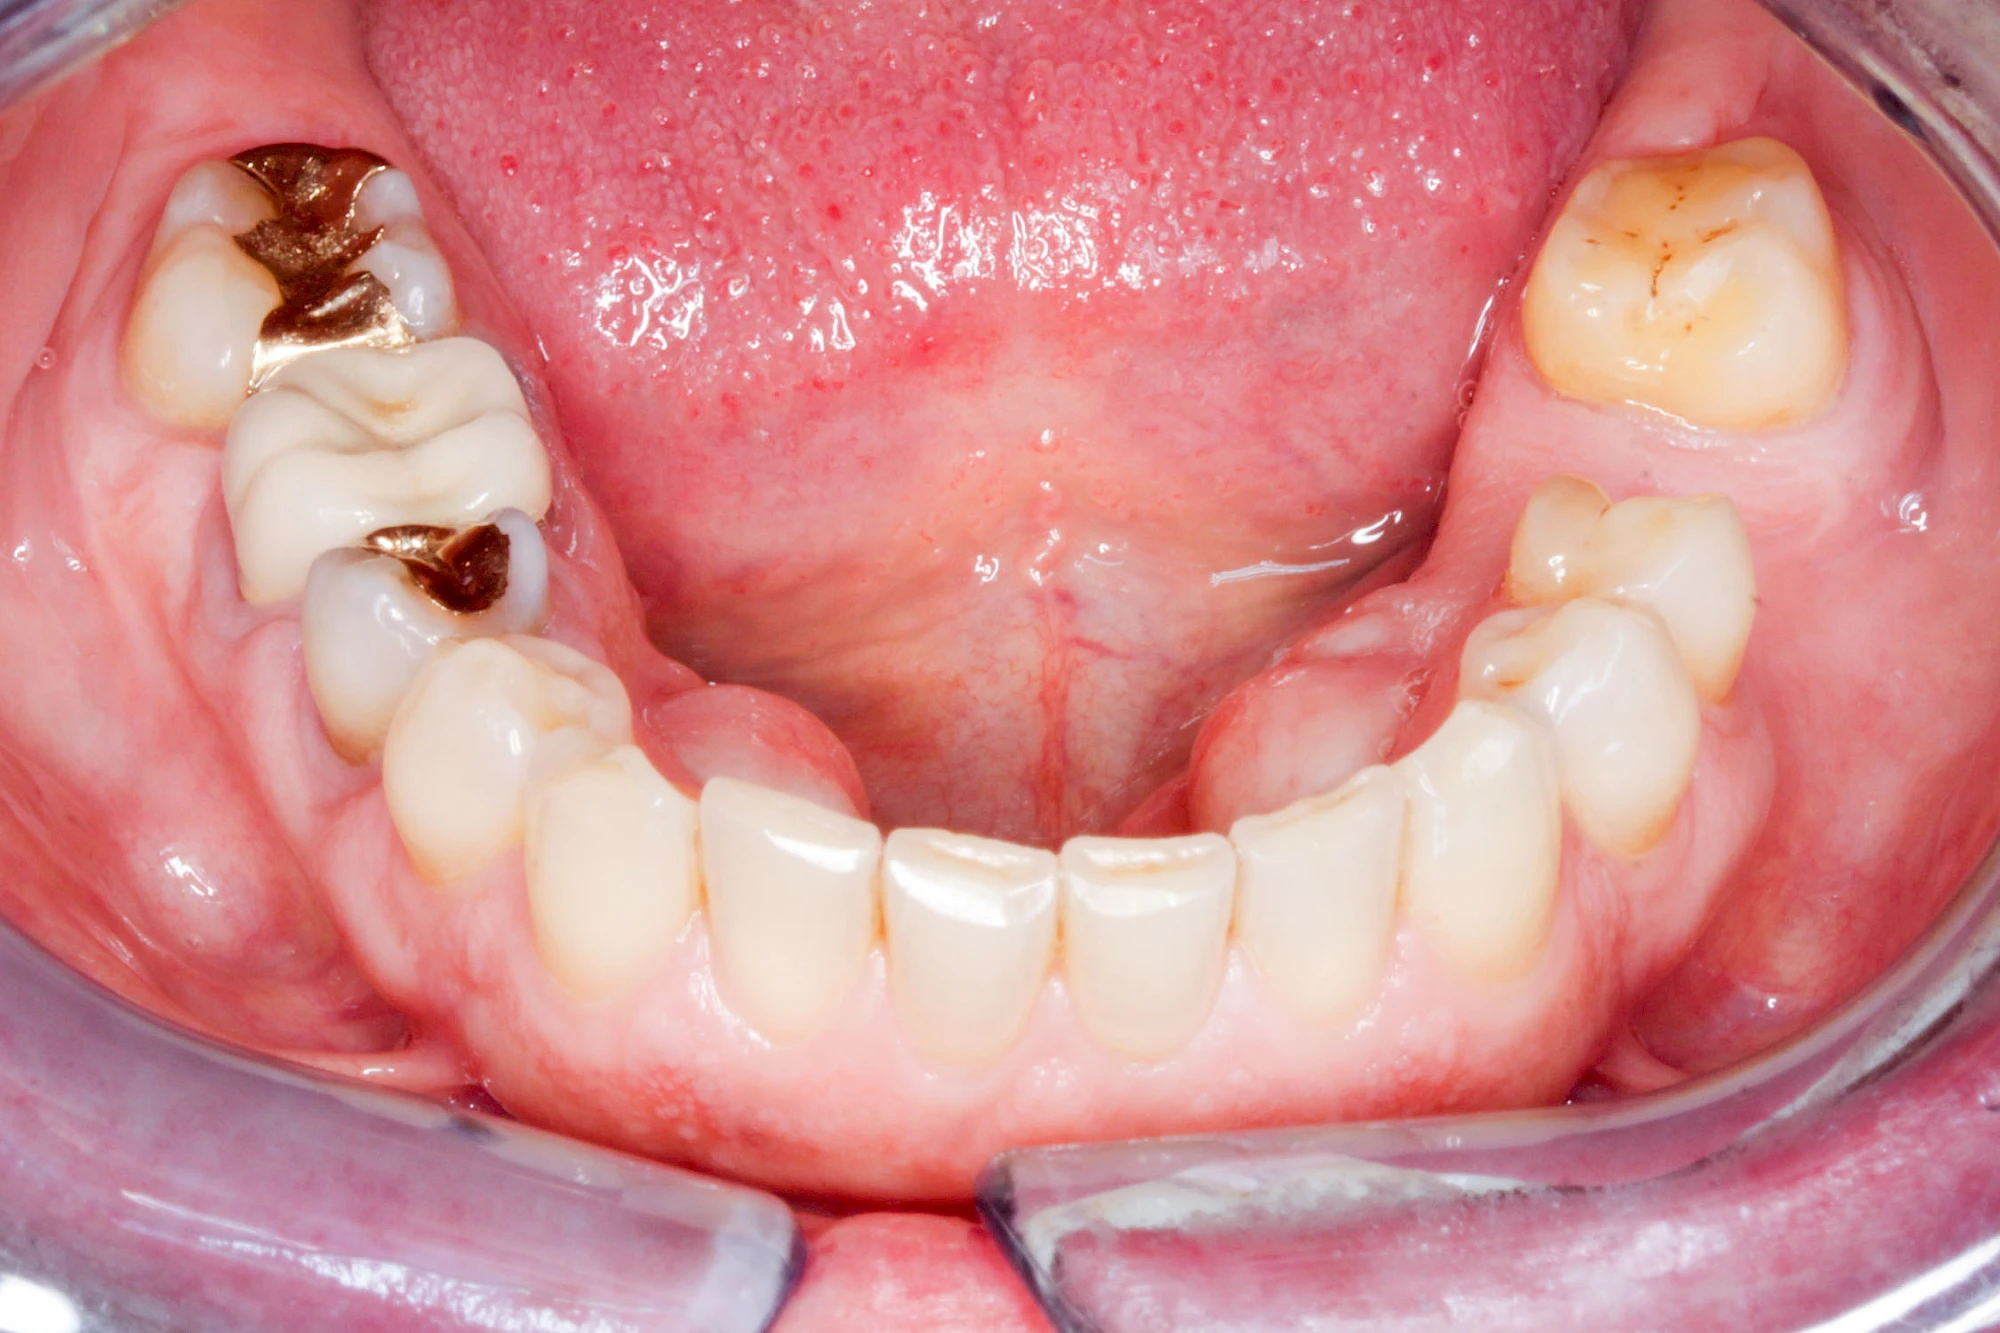

Lippen-Kiefer-Gaumenspalten (LKG-Spalte) sind angeborene Fehlbildungen im Mund-Kiefer-Gesichtsbereich. Die Gewebestrukturen im Bereich des Oberkiefers sind im Zuge der Entwicklungen bis zur Geburt nicht zusammengewachsen. Diese Fehlbildung zählt zu den häufigsten Fehlbildungen des Menschen, von 500 Neugeborenen ist eines betroffen. Die Fehlbildungen können sich auf Lippe, Gaumen und Kiefer allein beschränken, treten häufig aber kombiniert und in seltenen Fällen sogar beidseits auf.

Heute werden in Deutschland Menschen mit Lippen-Kiefer-Gaumenspalten bereits ab Geburt von Experten verschiedener Fachrichtungen (Mund-Kiefer-Gesichtschirurgen, Kieferorthopäden, Logopäden) betreut, damit entsprechende Korrekturen schon frühzeitig erfolgen können. Gerade jedoch bei älteren Menschen ist dies nicht immer geschehen. Diese Menschen tragen häufig technisch aufwendige Zahnprothesen.